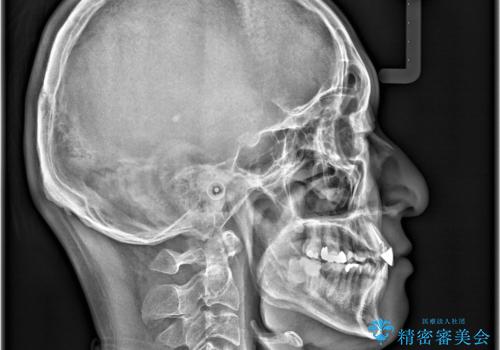

- 「八重歯と歯のでこぼこを治したい」を主訴に来院された患者様です。

歯は抜かずに奥歯の遠心移動とIPRで八重歯とでこぼこを改善しました。